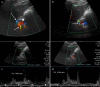

Fig. 7

B-Mode US: longitudinal sub-xiphoid scan of the abdominal aorta performed in supine decubitus. a Measurement of the aorto-mesenteric angle "A" in patient with NCS. Abdominal aorta (short arrow). Superior mesenteric artery (long arrow). b Duplex Doppler US shows a peak speed reduction in left renal vein. c Measurement of the left renal vein diameter. d Power Doppler US shows varicosity of the gonadal plexus (vein diameter 5.5 mm)